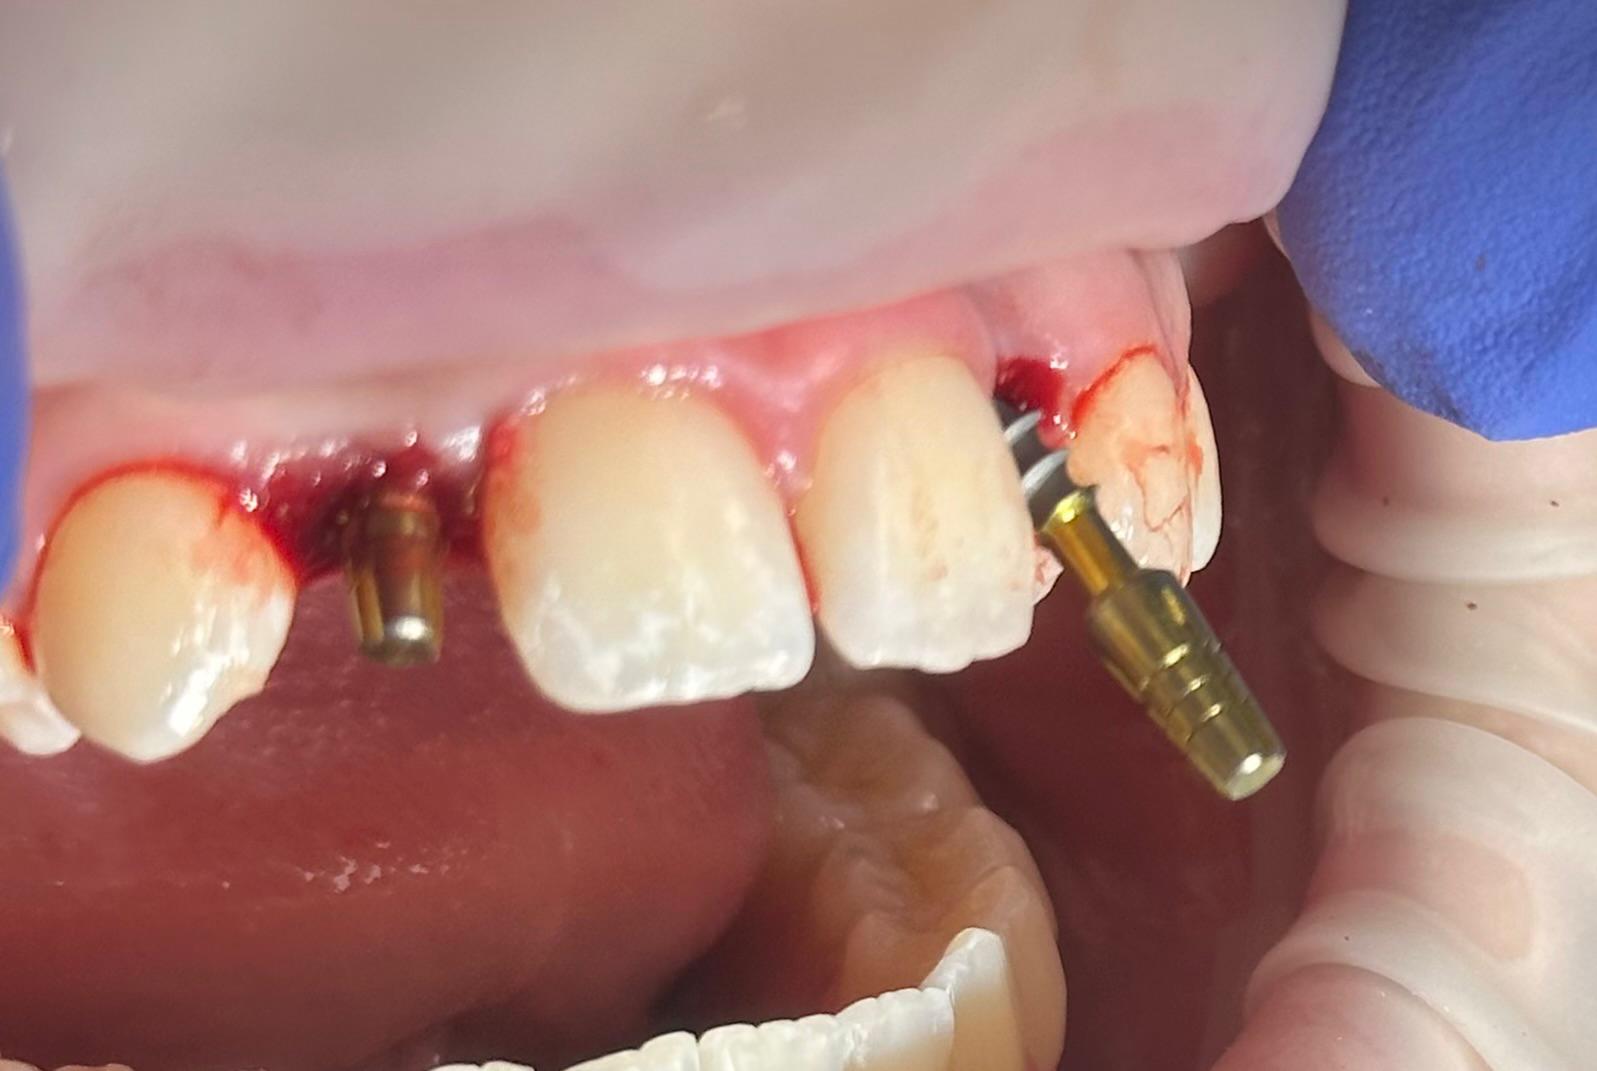

En lugar de abrir grandes heridas para colocar hueso artificial, utilizamos implantes de última generación conocidos como monobloque. Estos implantes están diseñados específicamente para ser colocados en espacios muy reducidos, aprovechando hasta el último milímetro de tu hueso natural.

Para nosotros, la precisión es innegociable. Antes de empezar, analizamos tu estructura ósea con tecnología de imagen avanzada. Esto nos permite ver lo que otros no ven y planificar una cirugía que apenas deja huella en tu organismo.

Lo que realmente nos diferencia es la carga inmediata. No queremos que salgas de nuestra clínica con un hueco en tu sonrisa. En el mismo momento de la cirugía, preparamos coronas provisionales que no solo devuelven la estética, sino que ayudan a que tu encía se cure con la forma perfecta.